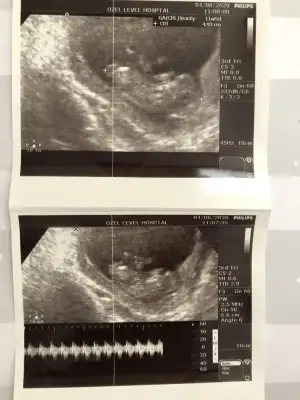

3 yorumunda erkek oldu 3 ayrı ultrason fotosunda bir kızım var hayırlısı olur inşallah doktor söylemedi cinsiyet bizim şubat grubunda herkese söylemiş doktorları bi ben öğrenemedim teşekkür ederim sağolErkek gibi![]()

Erkek dediErkek gibi nubu kafa şekli kız gibi13 hafta olursa paylaşın teyit ederim ❤

Erkek gibi olursa 13 hafta USG tekrar paylaşın USG net değil emin olamadimMerhaba. 11+5 teyim. Yorumlar mısınız![]()